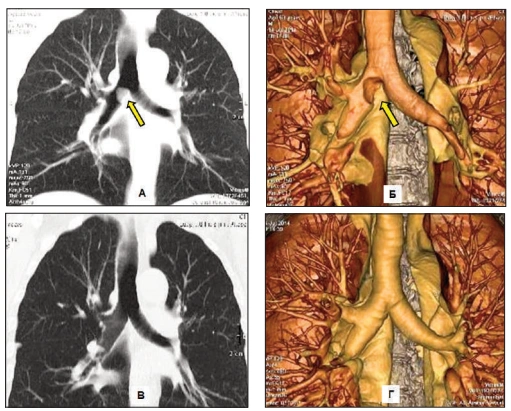

1. Severe lung damage - a life without breath

Over time, chronic inflammation and toxin buildup cause irreversible damage to the airways and lung tissue.

The lungs lose their ability to absorb oxygen efficiently. No quick remedy can restore what's been destroyed.

2. COPD progression - the silent suffocator

Untreated lung congestion and airway inflammation often develop into full-scale COPD.

It may begin with mild shortness of breath or an occasional cough-but the damage continues silently.

Before patients realize what's happening, their lung capacity has already declined significantly.